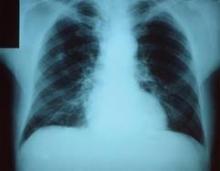

CDC Public Health Image Library

Sepsis or organ failure, not pneumonia, is often the principal diagnosis for hospitals’ sickest patients.